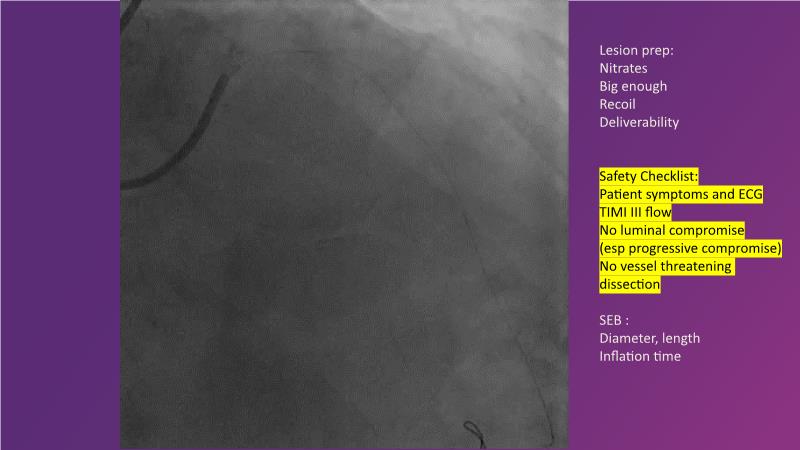

Explore the latest trends in percutaneous coronary intervention (PCI) in this session, focusing on stentless PCI and the role of sustained limus release technology. Join the discussion on how sustained limus release can expand the indications for drug-eluting balloons (DEB) and minimize the use of metal stents, gain insights into the importance of vessel preparation and learn which tools to utilize in specific scenarios.

- To learn about the importance of vessel preparation and which tool to use when

- To review clinical scenarios when a stent is not required